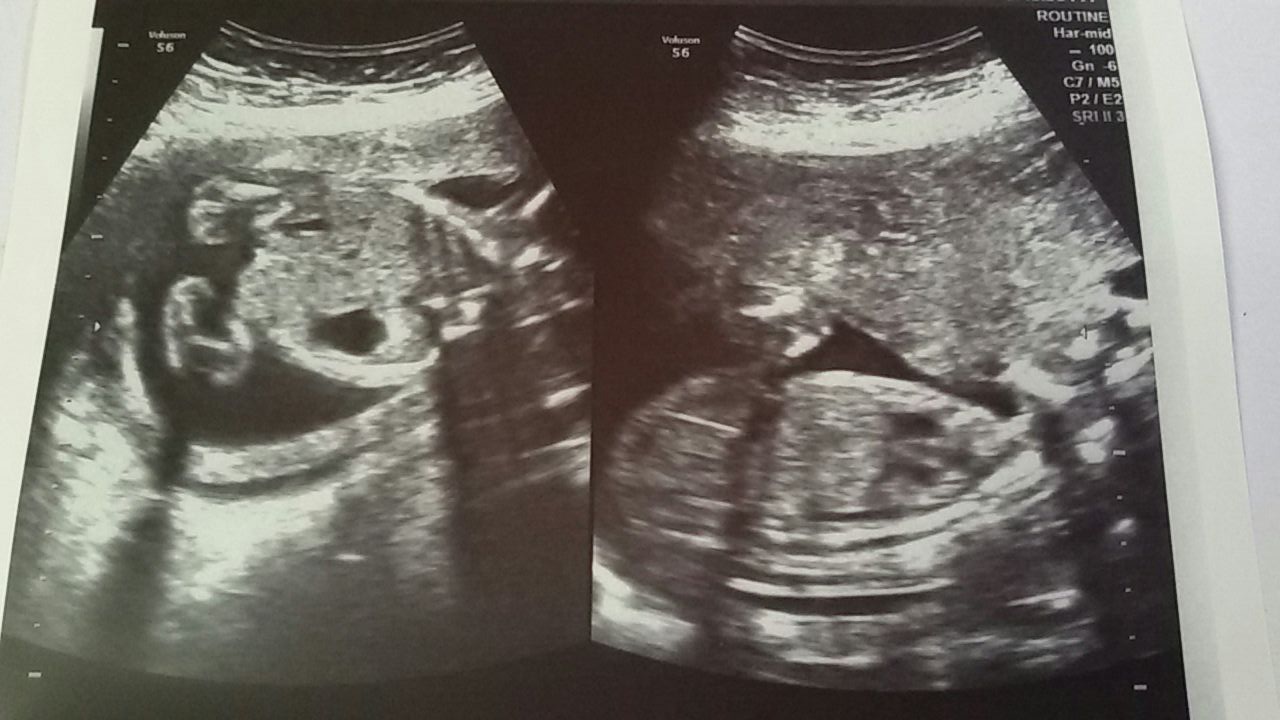

Attaching a pics from our 22nd week u/s.

Attachment 27201

But I thought the first one was a between the legs shot.If not i will upload more pics.

It looks like a girl if that is.